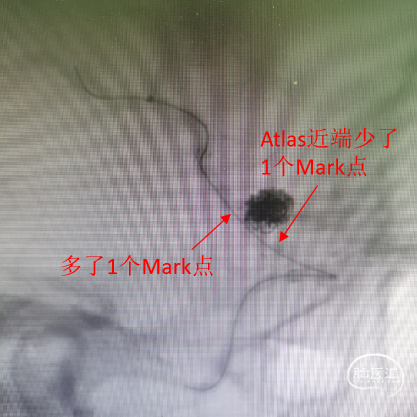

用导丝成袢带XT-27支架导管到位时卡住辅助支架近端Mark,前推XT-27增张后透视下发现辅助支架近端少了一个Mark点,疑似支架近端钢梁被XT-27推得内翻。XT-27顺利到位,预置在大脑中M2。

遇到问题:

是否继续放Evolve?万一被内翻的支架钢梁钳夹住打不开怎么办?面临抉择。

讨论后相信Evolve的支撑力,尝试先释放一部分FD后推挤系统增张,让Evolve充分鼓起贴壁,将内翻的钢梁压到血管壁上,如Evolve推不开则回收。